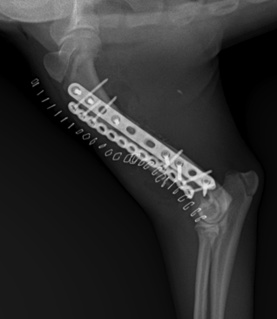

04 고난도 골절 수복 수술 (Surgical Procedure)

수술은 후추의 정상 뼈 구조 유합과 함께 빠른 회복과 정상 보행 회복에 초점을 맞추어 진행되었습니다.

1. Internal Fixation (내부 고정)

Rigid 플레이트를 이용하여 여러 조각으로 나뉜 뼈를 해부학적으로 정교하게 정렬하고 고정했습니다.

2. BMP(골 형성 단백질) 이식

BMP(골 형성 단백질)은 뼈 재생을 유도하는 단백질로, 골재생 보조 목적으로 임상에서 활용되고 있습니다. 복합 골절인 환자의 골유합을 촉진하기 위해 특수 골 형성 단백질을 이식하여 뼈가 더 빨리 붙을 수 있도록 해주었습니다.

강아지 상완골 골절 수술/ 출처: 에스동물메디컬센터

강아지 상완골 분쇄골절 수술 후 / 출처: 에스동물메디컬센터

05 골절 수술 후 경과

후추는 입원 기간 동안 술부 관리와 재활을 병행하였고 무사히 퇴원하였습니다. 퇴원 후 정기적인 재진 내원하여 체크하였을 때 보행 상태가 많이 회복된 모습을 보여주었습니다.

복합 골절은 자칫 평생 장애로 남을 수 있는 위험한 상황이었지만, 정확한 CT 진단 + 3D 프린팅 시뮬레이션 + 숙련된 집도의의 기술이 더해져 성공적인 회복 사례를 만들어낼 수 있었습니다.